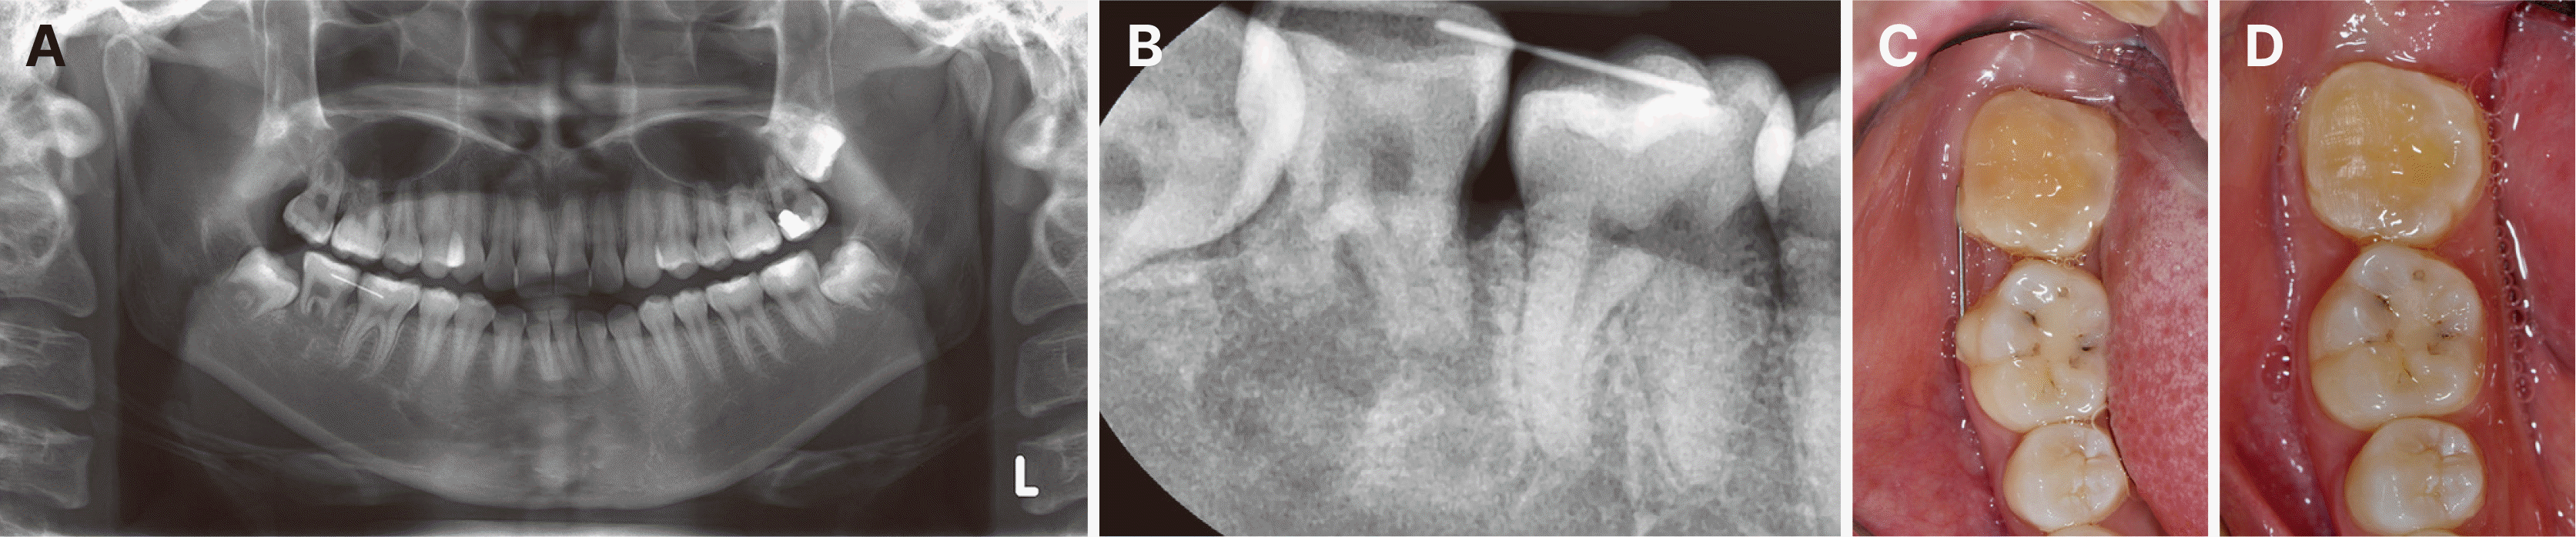

19세 여성 환자가 하악 우측 제2대구치의 이차 우식을 주소로 본원 치과보존과에 내원하였다. 초진 파노라마 방사선 사진에서 공여치가 될 상악 우측 제3대구치는 약 2/3 정도의 치근 발육을 보이고 있었으며, 수여부가 될 하악 우측 제2대구치 부위와의 관계를 확인할 수 있었다(Fig. 1A). 치근단 방사선 사진에서는 하악 우측 제2대구치의 레진 수복물 하방으로 치은연하까지 연장된 광범위한 이차 우식과 원심 치근단 부위의 방사선 투과상이 관찰되었다(Fig. 1B). 근관치료를 위한 와동 개방 시 원심측으로 치은연하까지 연장된 심각한 치질 소실이 확인되었다(Fig. 1C). 이에 하악 우측 제2대구치는 발치가 불가피할 것으로 판단하였고, 상악 우측 제3대구치를 자가치아이식의 공여치로 사용하기로 계획하였다. 이에 술 전 CBCT를 촬영하여 3차원적 평가를 시행하였고, 이를 바탕으로 computer-aided rapid prototyping (CARP) 기술을 이용하여 실물 크기의 복제 모형을 제작하였다.

Fig. 1

Initial radiographic examination and pre-operative clinical status. (A) Initial panoramic radiograph showing the relationship between the donor tooth (incompletely erupted maxillary right third molar with approximately two-thirds root development) and the recipient site (mandibular right second molar). (B) Periapical radiograph showing extensive secondary caries under resin restoration extending to subcrestal level and periapical radiolucency in the distal root apex area of the mandibular right second molar. (C) Access opening for endodontic treatment revealed severe distal tooth structure loss extending subgingivally at the distal aspect of the mandibular right second molar.